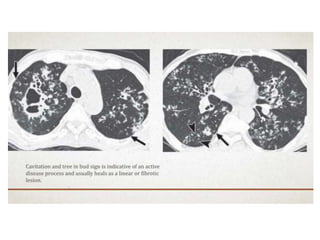

• HRCT findings in TB :-

• Consolidation anywhere, lymphadenopathy and

pleural effusion. Usually regresses to calcified lung

nodule.

• Cavitation

• (Endobronchial spread) Tree in bud appearance)

• Miliary TB: 2-3 mm nodules with random